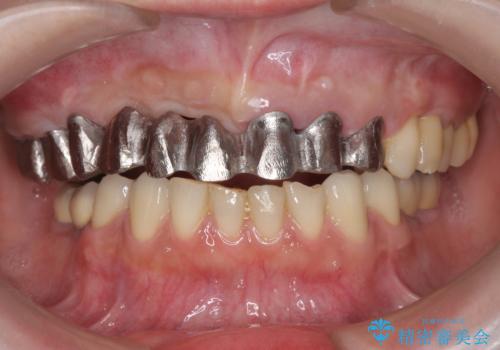

保存の難しい歯の抜歯、保存できる歯の歯周病治療、欠損部位の歯槽堤形態回復を含めブリッジによる安定した咬合機能回復を計画します。

- 90万円 (仮歯×9 メタルボンドクラウン×9)費用は治療当時の料金となります

ブリッジは欠損した部位に臨在する歯を削り、被せなければいけないというデメリットがありますが反面噛む力が強い場合連結することで強大な咬合力に対抗できるというメリットも存在します。